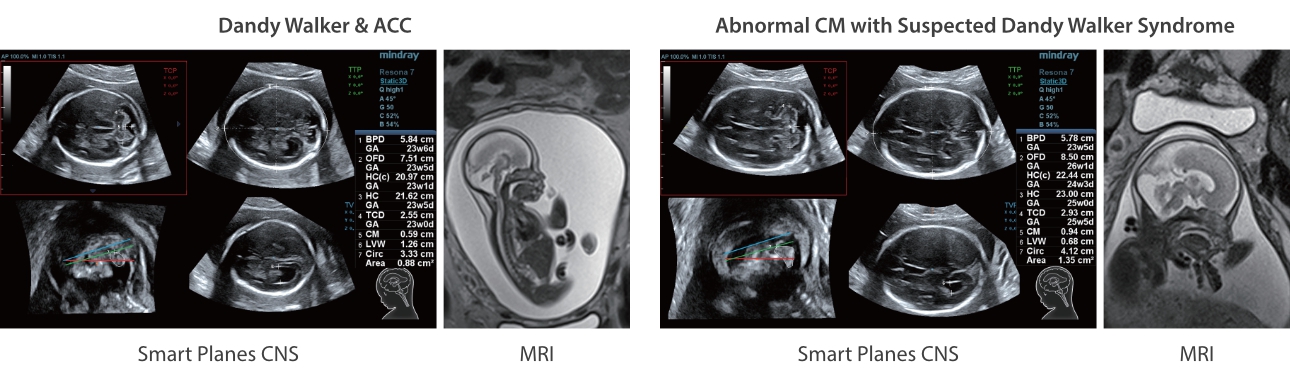

?? ??? ??

Mindray? ??? ??? ?? ??? ???? ??? ?? ??? ??? ????? ??? ????. ?? ???? ZONE Sonography? ??? ???? ?? Resona 7? ??? ZST+ ???? ?? ?? ? ?? ??? ????? ?? ??? ??? ??? ? ?? ????.

?? Resona 7? ???? ??? ?? ???? ??? ??? ???? ??? ?? ???? V Flow? ?? CNS ??? ?? 3D ??? ???? ?? ???? ?? ??? ?? ?? ?? ??? ??????. ???? ??? ??? ?? ?? ??? ??? ?? ?? ??? ??? Resona 7? ??? ???? ???? ??? ??? ??? ????.